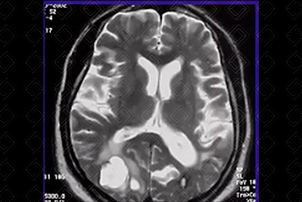

Texto alternativo para a imagem Figura 1. Créditos: Dra. Elazir Mota - Rio de Janeiro/RJ

Descrição da figura 1: Imagem espontaneamente densa no putâmen direito com halo de edema circunjacente (seta vermelha), compatível com sangramento, em paciente hipertenso.

• Hemorragia hipertensiva: Hematoma focal agudo ou micro-hemorragias. Localizações mais comuns: putâmen e cápsula externa (mais comuns, cerca de 60-65% dos casos). Outras localizações típicas são tálamo, centro semioval, cerebelo e ponte (f iguras 1 e 2);